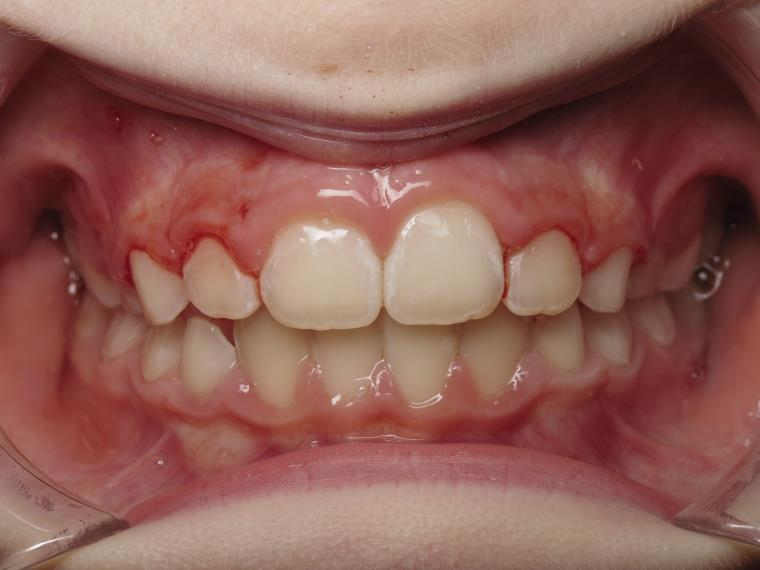

sectionnel multibagues

surveillance évolution de la dentition pendant 4 ans

bilan début fin de traitement